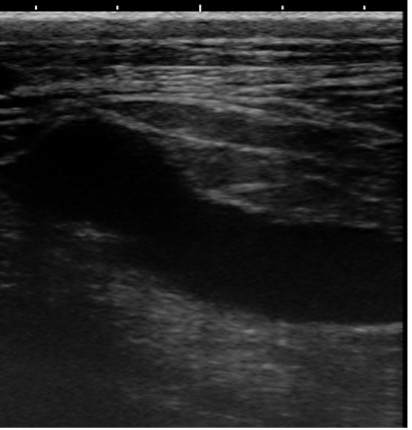

断面③④

腫瘤①に巻き込まれた尿管は、断面②と比較すると押しつぶされるようにして狭窄しています。

以上の画像と触診から、腫瘤①が尿管を巻き込むように形成されており、巻き込まれた尿管は著しく狭窄し(③④)、腎盂および腫瘤より腎臓側の尿管は鬱滞した尿により著しく拡張している(①②)ことがわかりました。